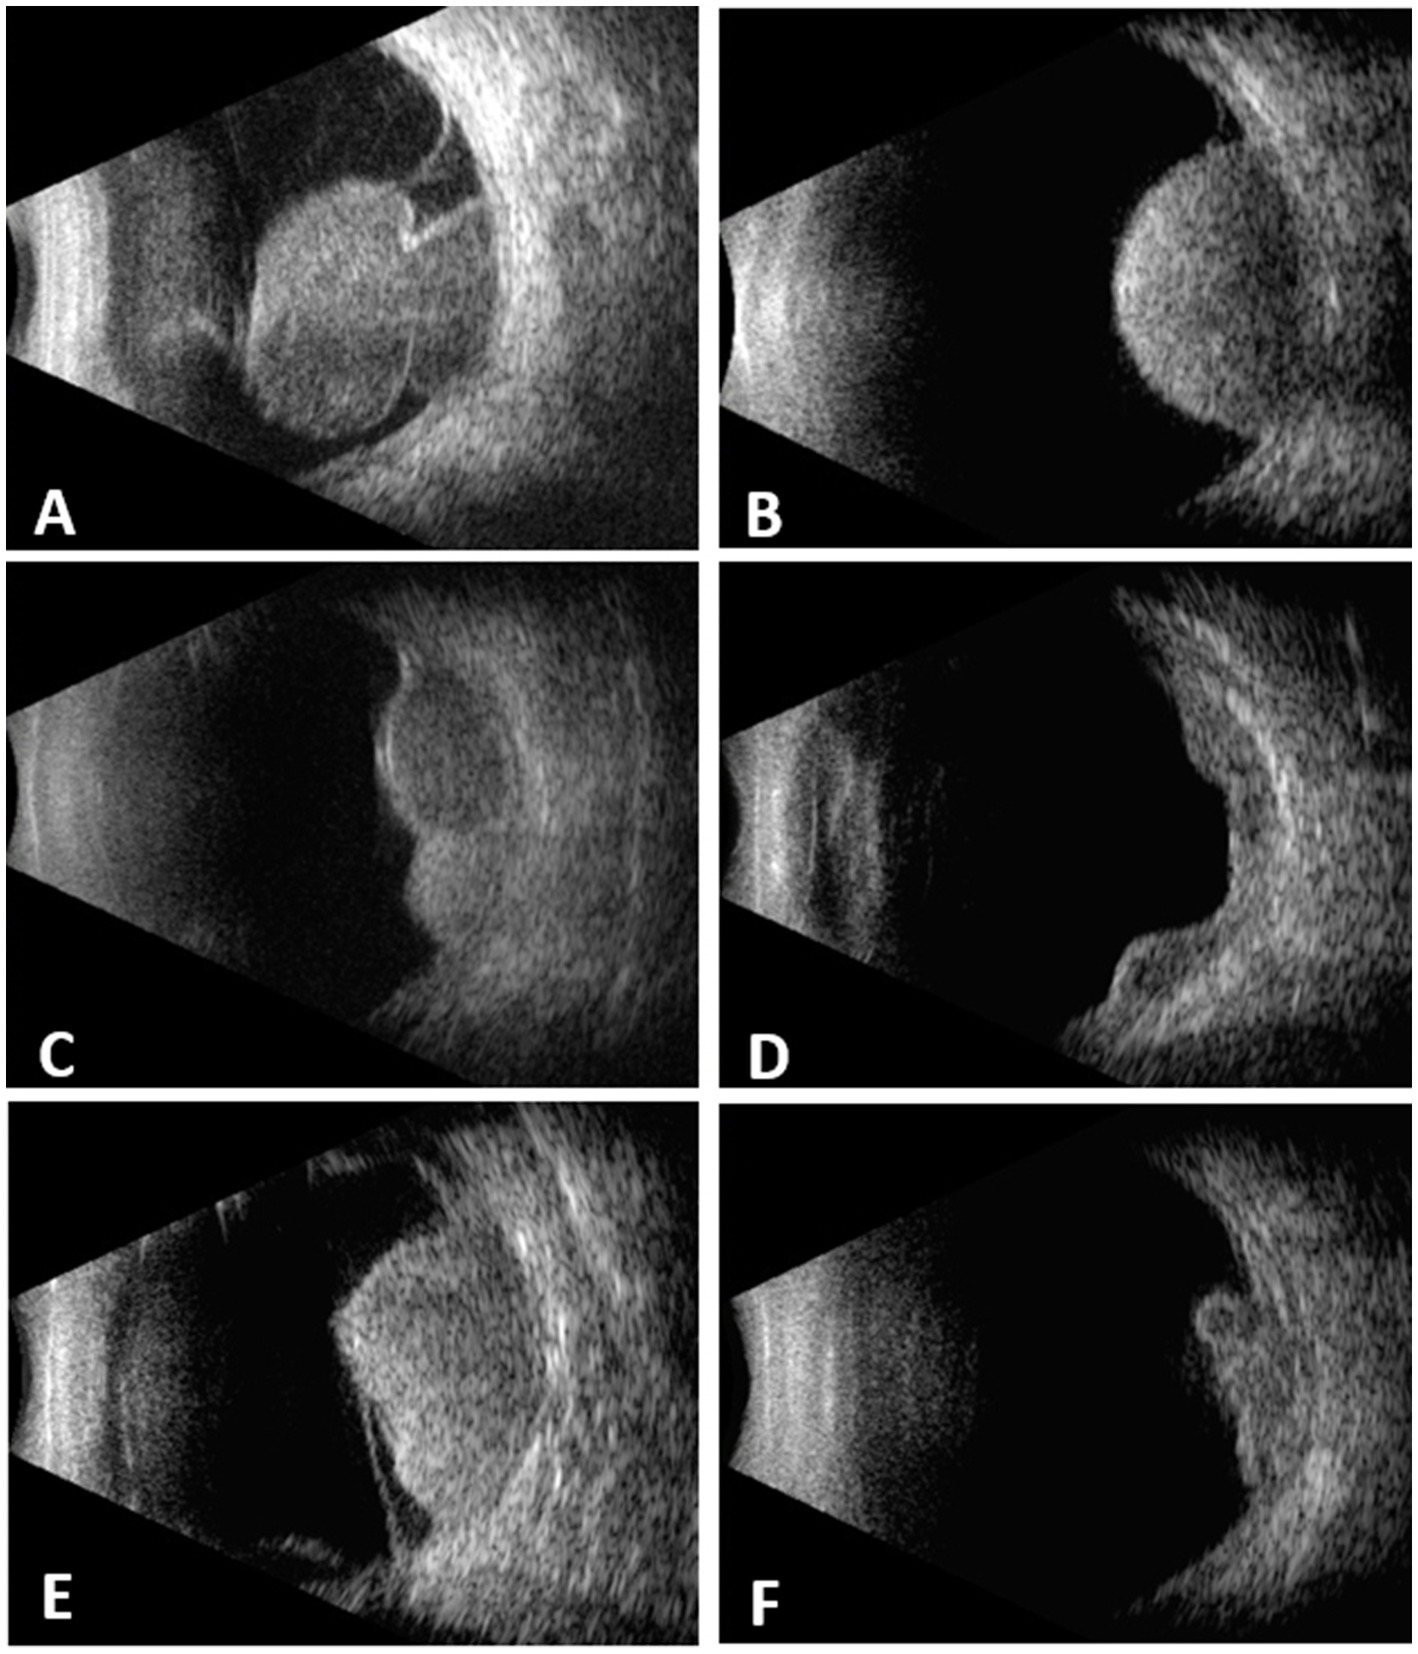

A total of 439 cases were included. 218 (49.7%) were female and 221 (50.3%) were male. The mean age at diagnosis was 51.4 ± 13.7 years (7–83). The tumor shape was mushroom in 164 (37.4%), dome in 129 (29.4%), lobulated in 62 (14.1%), diffuse in 11 (2.5%) and irregular in 73 (16.6%) (Figure 1). The mean tumor thickness was 8.9 ± 3.1 mm (2.7–21.0) and mean LBD was 13 ± 4 mm (4.9–25.0).

Figure 1

Choroidal melanomas with different configurations demonstrated on B-scan echograms. (A) mushroom. (B) dome. (C) lobulated. (D) diffuse. (E) irregular. (F) irregular.